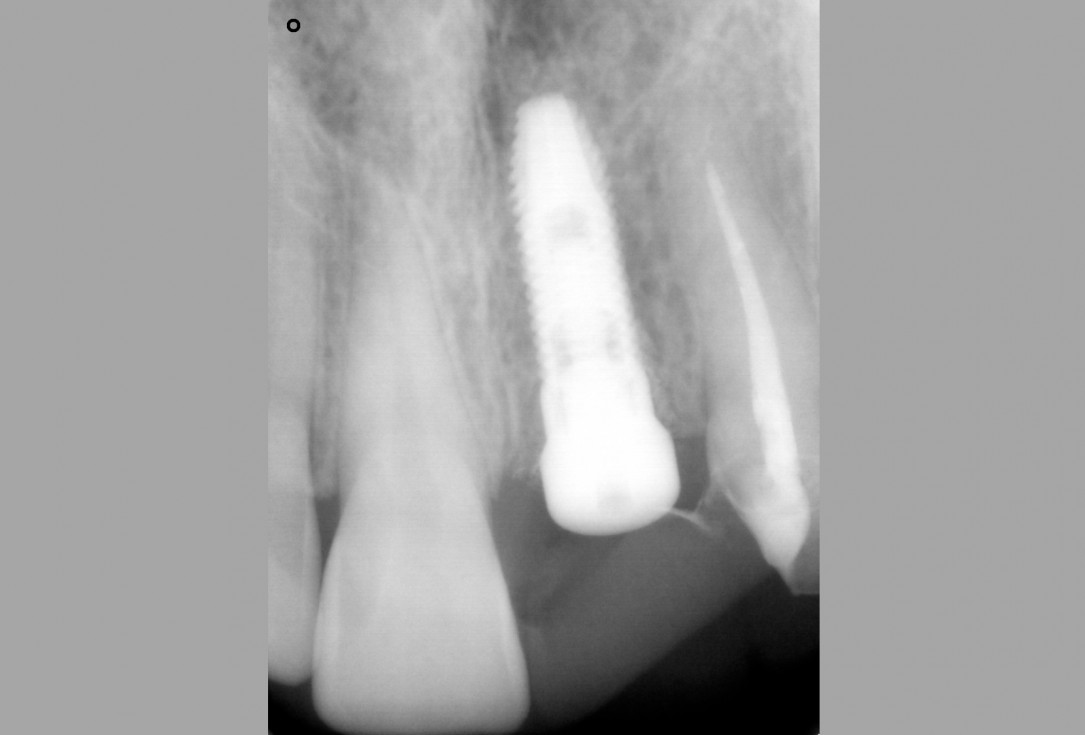

06/16 - X-ray control after filling of socket

Socket preservation with cerabone® - Dr. R. A. Nader